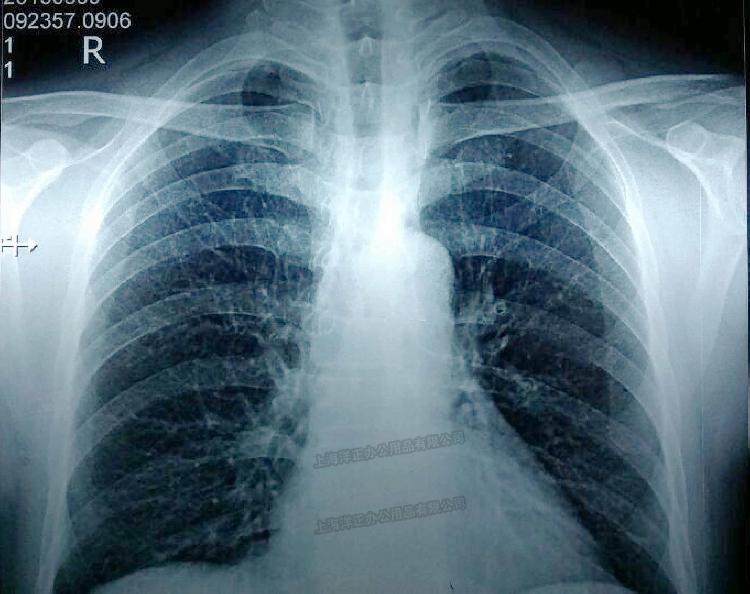

胸部x射线 ct增强片 帮帮忙看一下 是肺癌吗?

【读片】肺癌? [病例帖]

【读片】右肺上叶中央型肺癌,前纵隔囊性密度影是什么结构 [病例帖]

肺癌肉瘤x线-ct病例图片影像诊断分析!